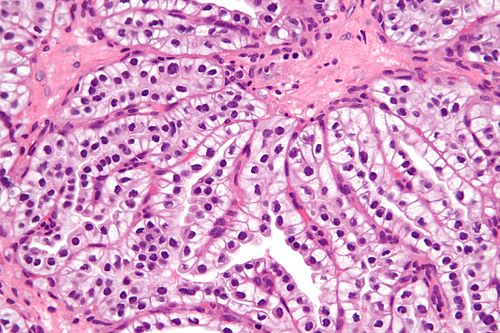

62 year old woman, renal mass.

High magnification. H&E stain.